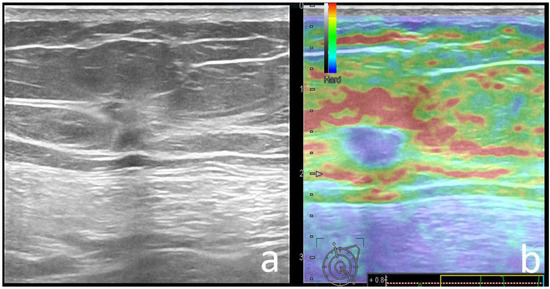

| Strain Elastography | 0.029 | ||

| Soft | 40 (40), 9 BGR | 30 (20.6), 1 BGR | |

| Hard | 58 (60) | 115 (79.3) | |